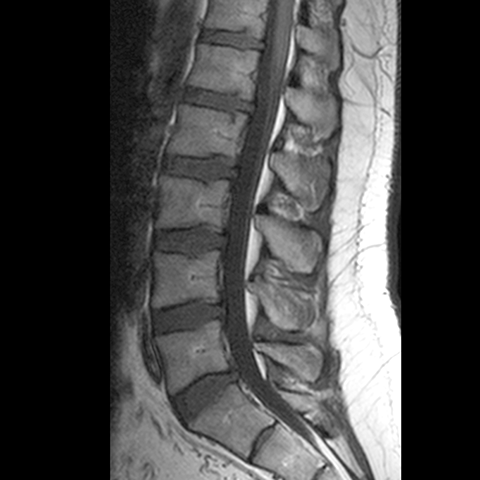

Lumbar Spine (MRI) [4 of 4]